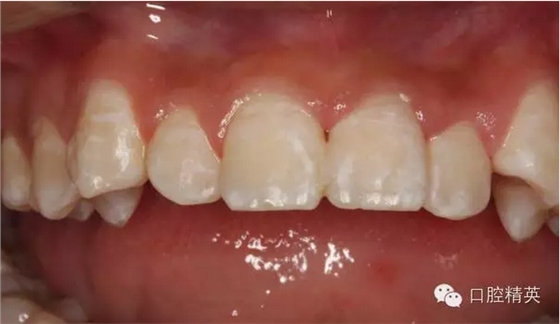

圖1.術(shù)前患者口內(nèi)像、牙槽窩輕度收縮、血凝塊穩(wěn)定、無滲出。

圖2.口內(nèi)整體影像